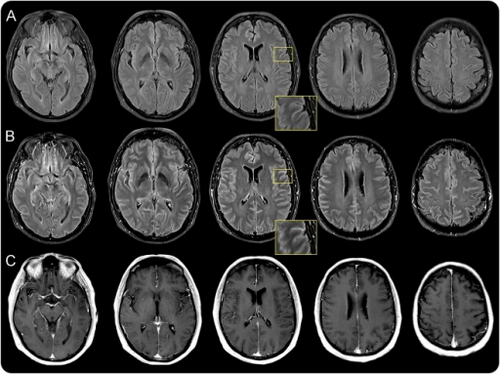

MRI of individual with viral meningitis caused by varicella-zoster virus a) Unenhanced precontrast FLAIR images b,c) FLAIR and postcontrast T1-weighted MRI

The diagnosis of viral meningitis is made by clinical history, physical exam, and several diagnostic tests.[22] Kernig and Brudzinski signs may be elucidated with specific physical exam maneuvers, and can help diagnose meningitis at the bedside.[16] Most importantly however, cerebrospinal fluid (CSF) is collected via lumbar puncture (also known as spinal tap). This fluid, which normally surrounds the brain and spinal cord, is then analyzed for signs of infection.[23] CSF findings that suggest a viral cause of meningitis include an elevated white blood cell count (usually 10-100 cells/µL) with a lymphocytic predominance in combination with a normal glucose level.[24] Increasingly, cerebrospinal fluid PCR tests have become especially useful for diagnosing viral meningitis, with an estimated sensitivity of 95-100%.[25] Additionally, samples from the stool, urine, blood and throat can also help to identify viral meningitis.[23] CSF vs serum c-reactive protein and procalcitonin have not been shown to elucidate whether meningitis is bacterial or viral.[15]